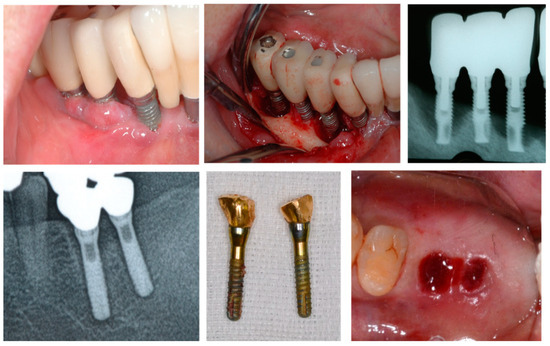

4.2.1. Relationship between Alveolar Ridge Augmentation, Complications, and Early Failure